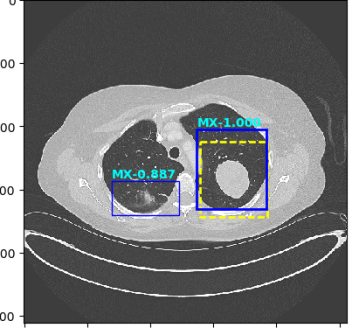

Figure 4: Six sample detection results are illustrated with the annotation lesion patches as yellow dashed boxes. The outputs from our proposed detection framework are shown in colored boxes with LiVer lesion (LV) in Red, Lung Nodule (LN) in Orange, ABdomen lesion (AB) in Green, Chest Lymph node (CL) in magenta and other MiXed lesions (MX) in blue. (a) Four lung lesions are all correctly detected; (b) Two lymph nodes in mediastinum is presented; (c) A Ground Glass Opacity (GGO) and a mass are detected in the lung; (d) An adrenal nodule; (e) Correct detections on both the small abdomen lymph node nearly aorta but also other metastases in liver and spleen; (f) Two liver metastasis are correctly detected. Three lung metastases are detected but erroneously classified as liver lesions .